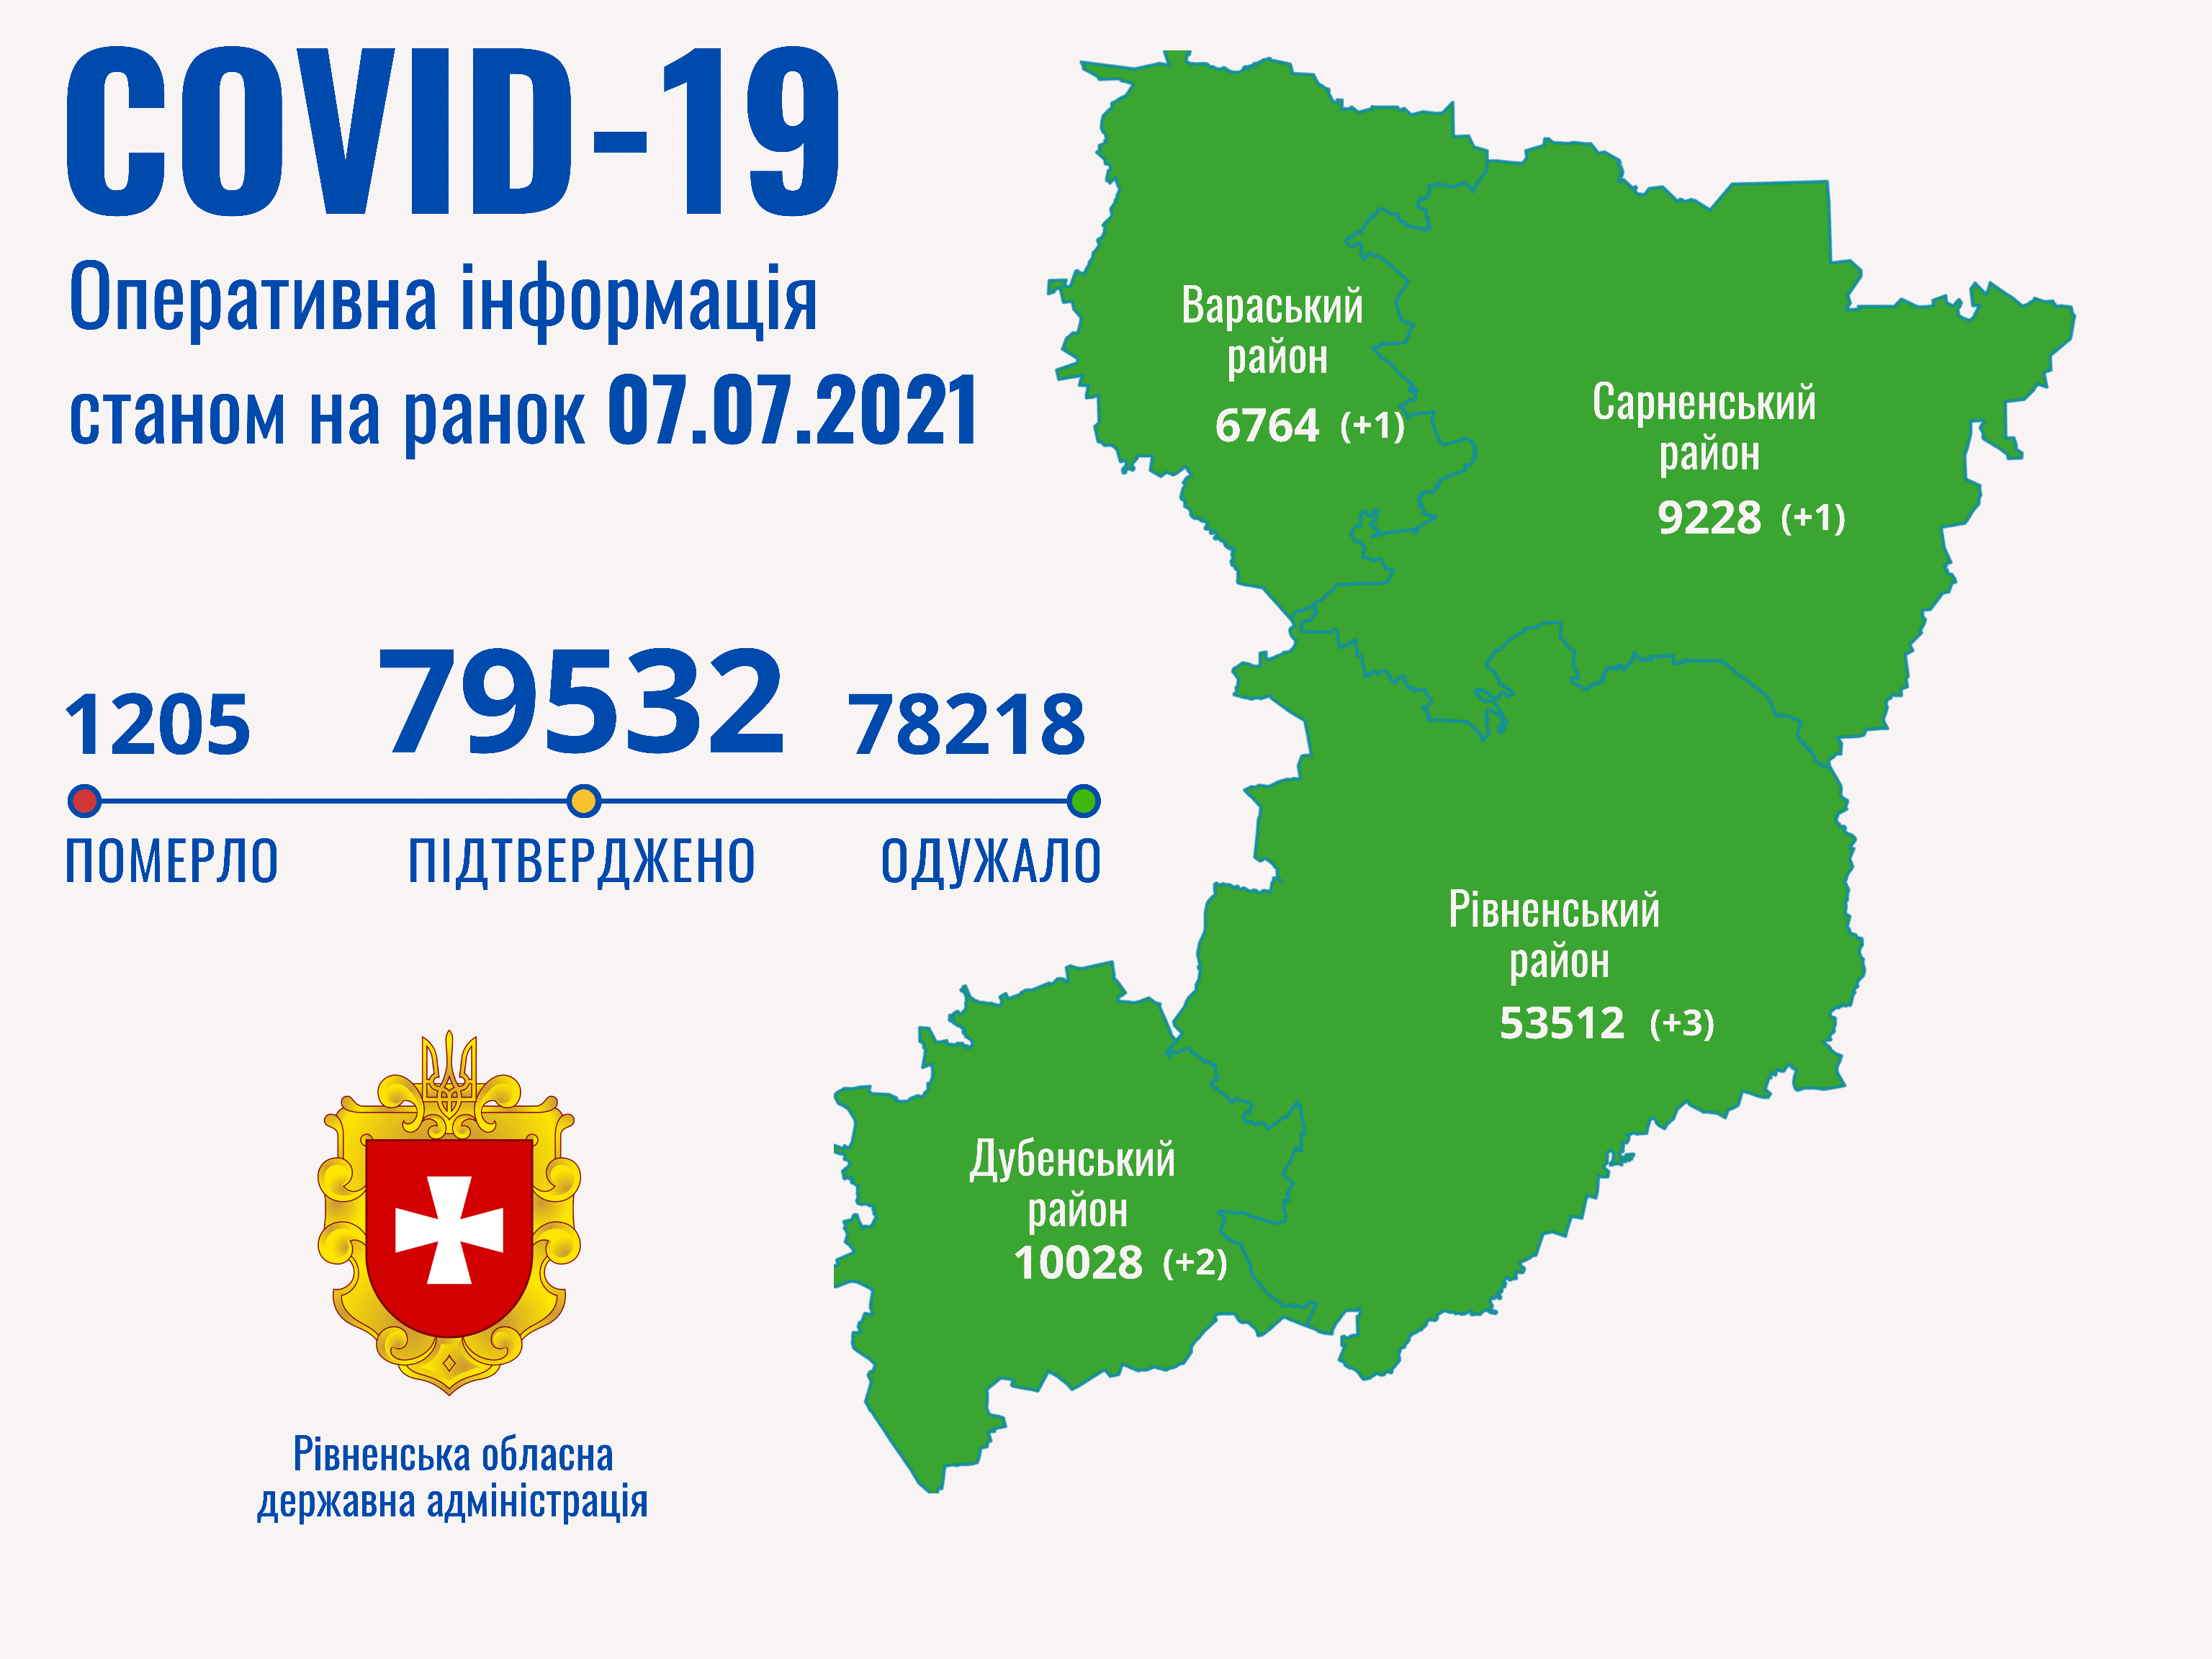

Пів тисячі - у важкому стані, 9 жителів Рівненщини померли за добу від коронавірусу